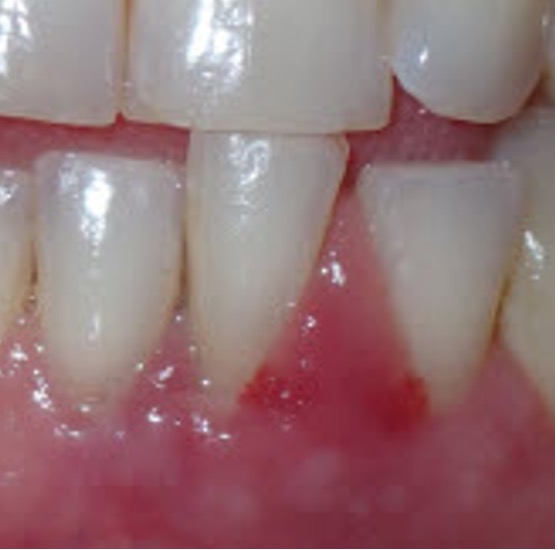

She was hitting tooth #24 every time she closed her mouth—and it hurt badly. The gingival tissue was visibly swollen, and the tooth had Class III mobility.

Radiographs showed severe bone loss. At first glance, this looked like a tooth destined for extraction.